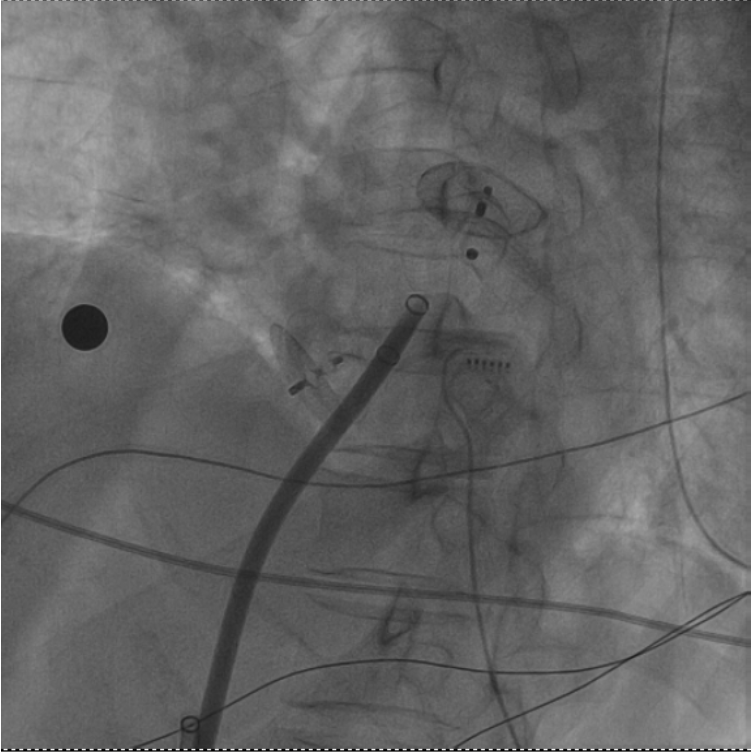

• 一次穿刺行兩個(gè)手術(shù)!十堰人醫(yī)成功消除圓孔封堵術(shù)后的房顫與血栓

一次穿刺行兩個(gè)手術(shù)!十堰人醫(yī)成功消除圓孔封堵術(shù)后的房顫與血栓

湖北日?qǐng)?bào)客戶端訊(通訊員馬婷婷、劉柳)近日,十堰市人民醫(yī)院心血管內(nèi)科一病區(qū)成功為一位特殊患者實(shí)施了房顫射頻消融加左心耳封堵術(shù)。值得一提的是,朱女士此前已接受過卵圓孔未閉封堵術(shù)及腦梗塞取栓術(shù),此次手術(shù)的成功,不僅彰顯了該…